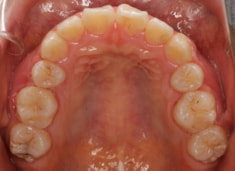

治療後(2年後)